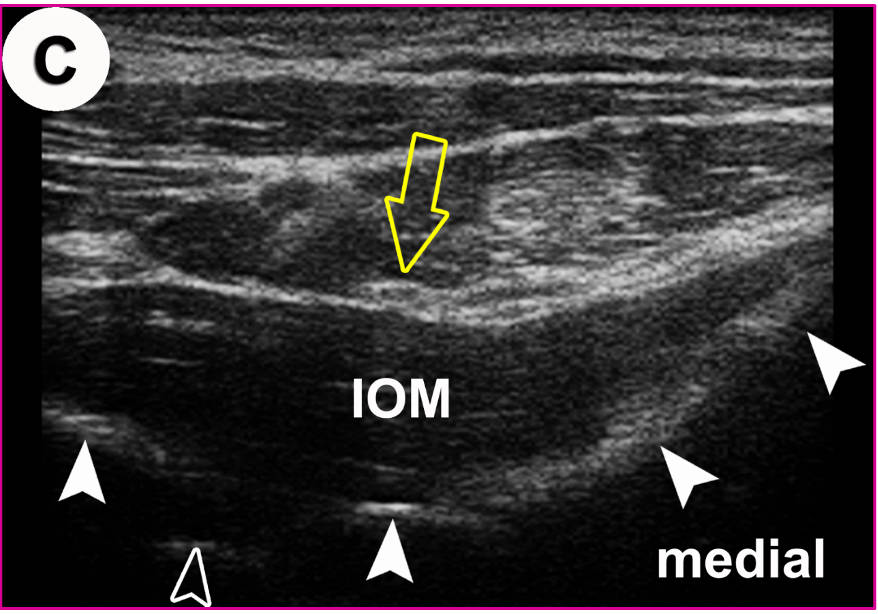

Anatomischer Transversalschnitt (A) und korrespondierendes US-Bild (B) auf Ebene des Foramen sacrale posterius secundum (II): Grundlage für die US-gezielte Injektion des Iliosakralgelenkes (ISG).

In der US-Darstellung ist der dorsalste Anteil des ISG einsehbar (offener Pfeilkopf). Der Spalt entspricht dem radiologischen Gelenkspalt! Die knöchernen Landmarken (gefüllte Pfeilköpfe) sind aber in allen Details deutlich zu erkennen (von medial nach lateral): Crista sacralis mediana, II, Crista sacralis lateralis, Facies glutea ossis ilii.